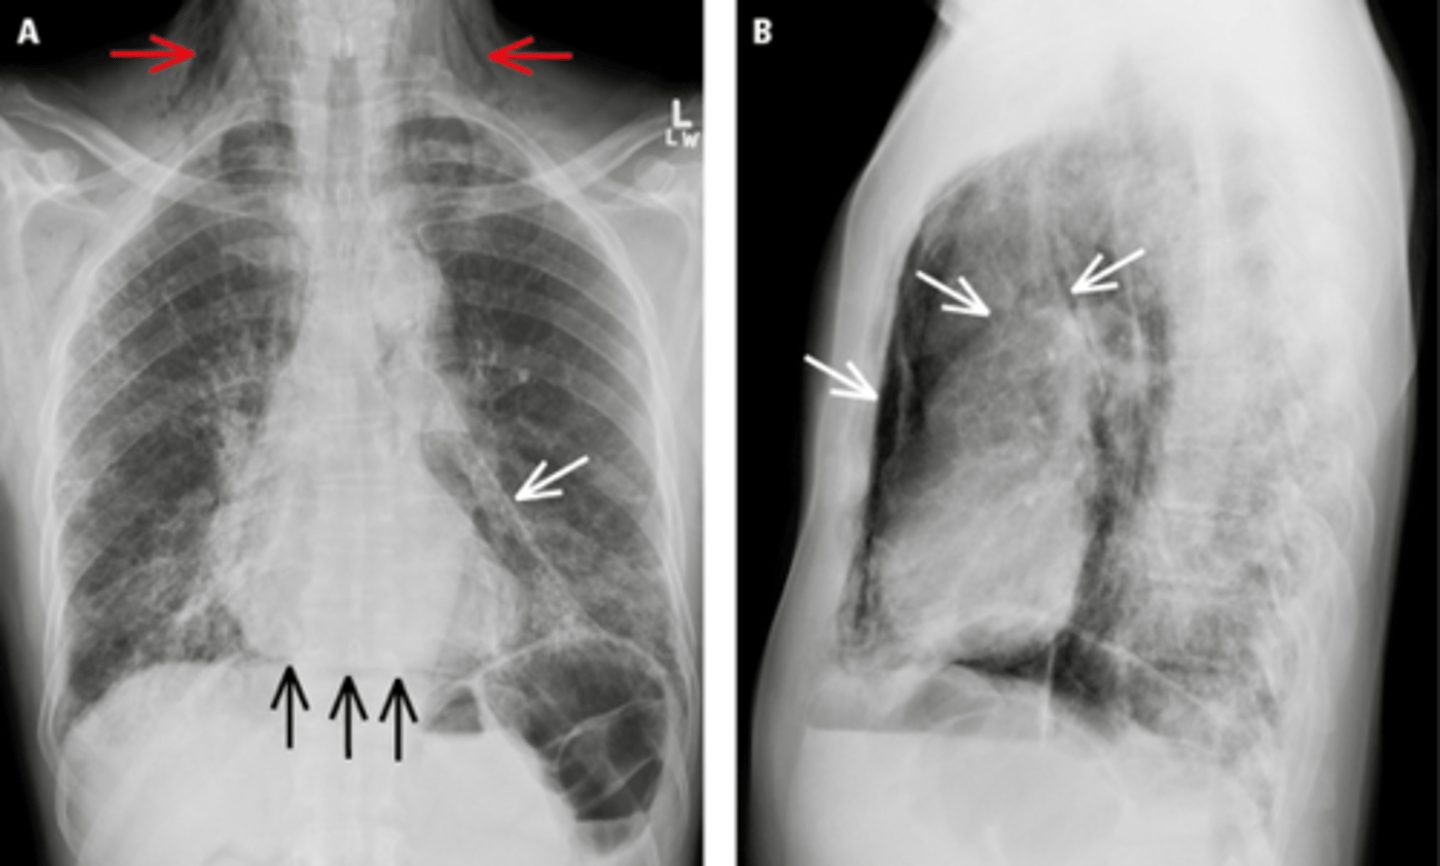

Pneumomediastinum (mediastinal emphysema)

knowt flashcard image

Pneumomediastinum